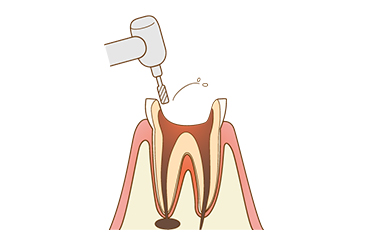

【1】感染部分を削る

-

虫歯菌が感染している組織を削って除去します。医師による目視のほか、歯科用CTなども活用します。

【2】神経の除去

-

感染した神経を露出させて除去します。根管内は細く複雑な形状をしているため専用器具を使用します。

【3】根管の拡大

-

根管内に薬剤を詰めやすくするために、根管を削って拡大します。